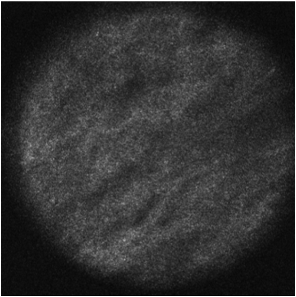

The dataset was collected in a previous study conducted at the University Hospital Schleswig-Holstein in Lübeck where expert assessment of CLM images in the colon area was evaluated ellebrecht2018confocal . A custom intraoperative device with integrated CLM (Karl Storz GmbH & Co KG, Tuttlingen, Germany) was built. The image resolution was pixels which covers a field of view of . In the study, ten rats received colon adenocarcinoma cell implantation in the colon and peritoneum with a growth time of seven days. Then, laparotomy was conducted and images of healthy colon tissue, malignant colon tissue, healthy peritoneum tissue and malignant peritoneum tissue were obtained. Example CLM images for each tissue type are shown in Figure 3. After removal of low quality images, 1577 images remained with 533 belonging to class HC, 309 belonging to class MC, 343 belonging to class HP and 392 belonging to class MP. Note that some subjects are missing classes such that, on average, six subjects per class remain. Ground-truth annotation of all images was obtained by tissue removal of the scanned areas and subsequent histological evaluation.